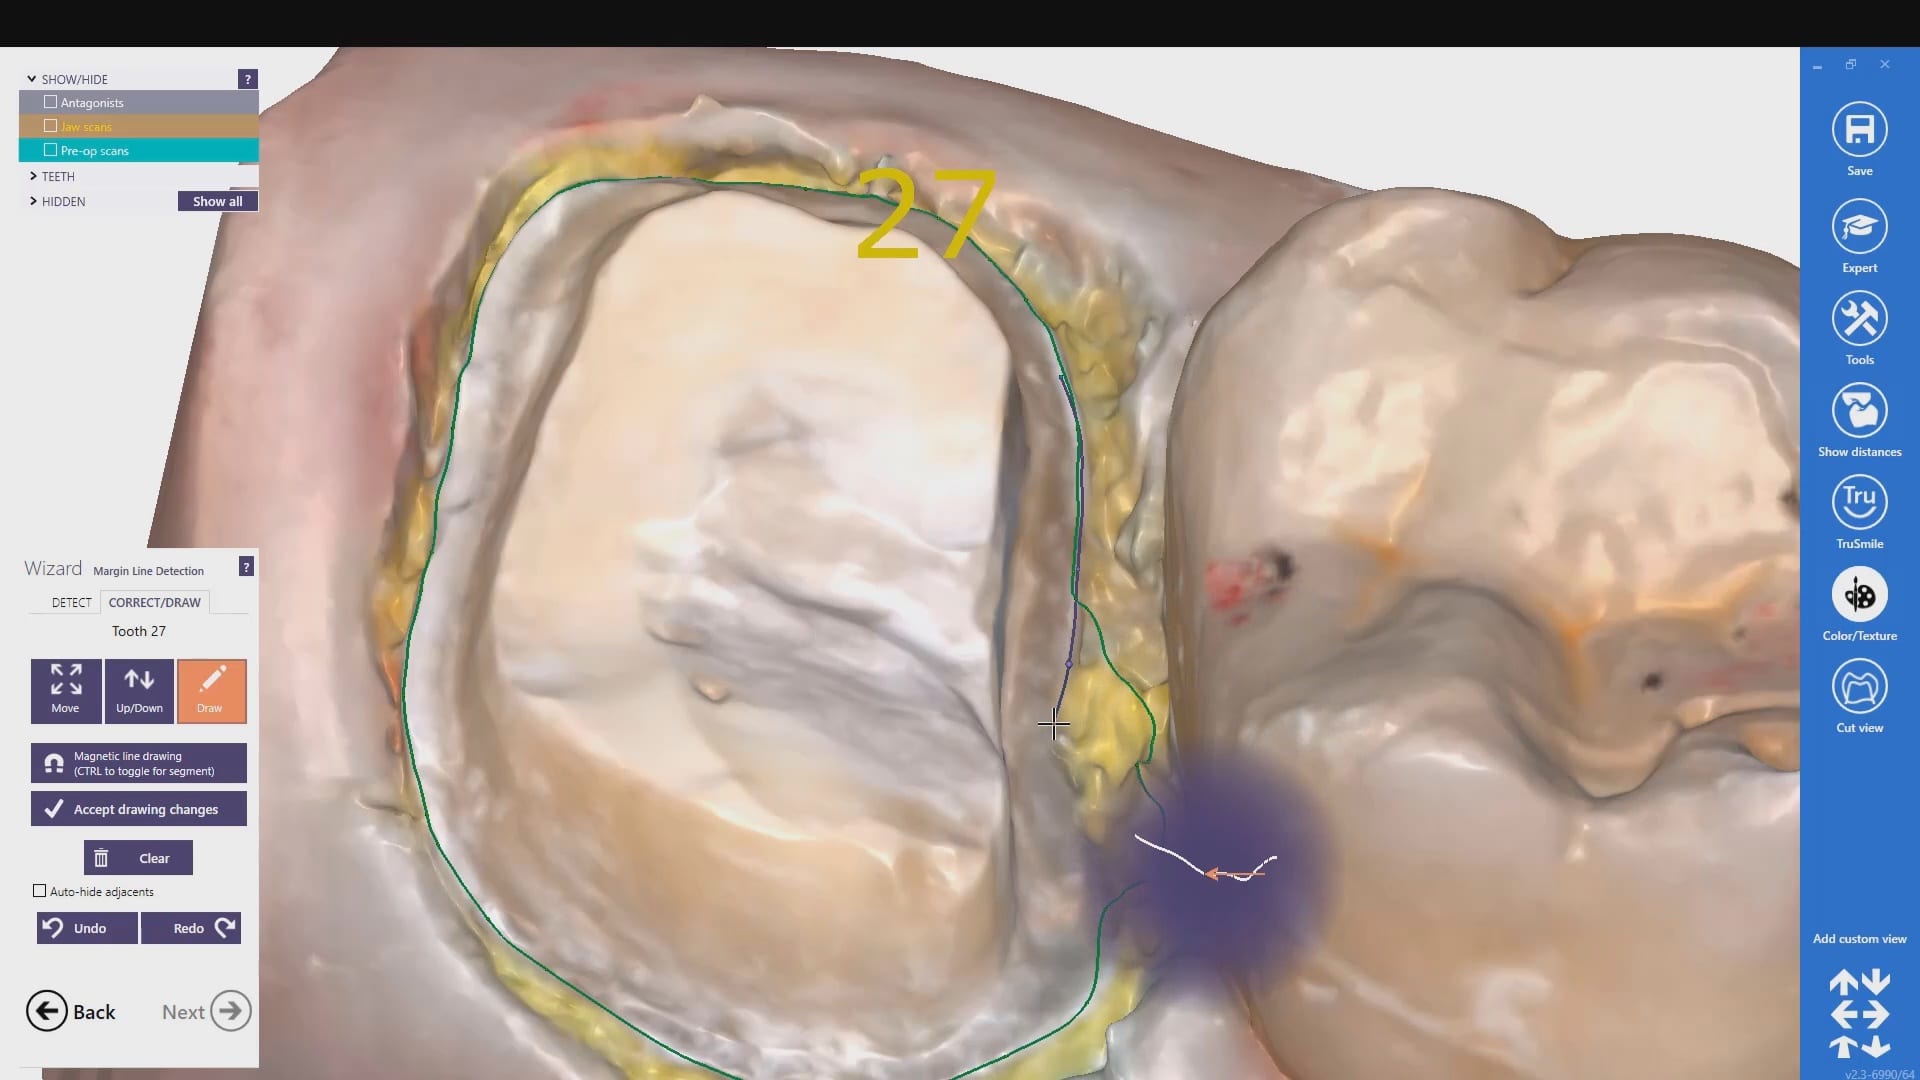

With analog dental impressions, it is imparative to separate the gum tissue from tooth structure and to create a trough for flash for dye work. This is not the case with the intra-oral scanner by Medit. All you need to do is displace the tissue so you have a clear line of site to the margins, and you just need to be flush. You don’t need flash like you do with stone work